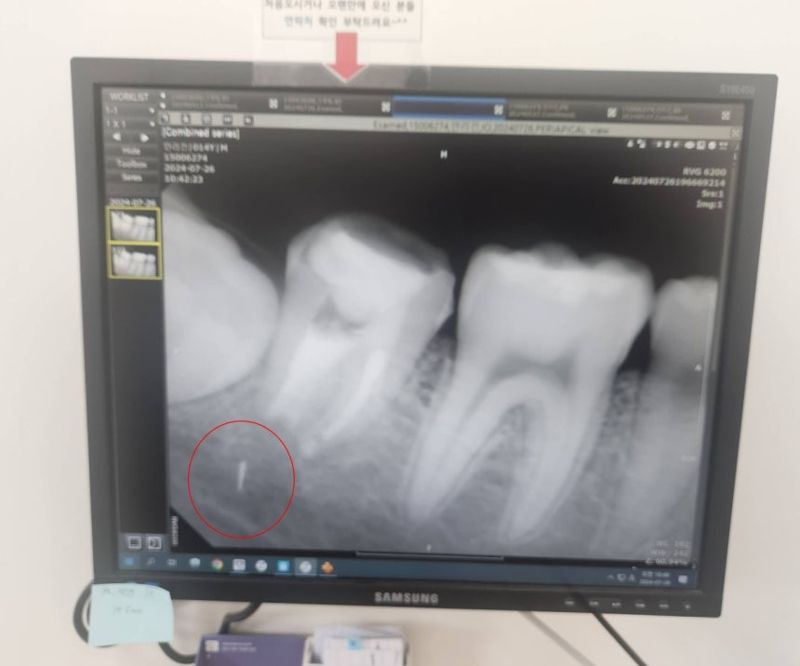

2일 연합뉴스에 따르면 사건은 지난 2024년 4월 경기 구리시 한 동네 치과의원에서 발생했다. 당시 중학교 3학년이던 황모(49)씨의 아들 안모(17)군은 치과 치료 후 통증과 염증에 시달렸다. 이에 한 달여 뒤 엑스레이를 촬영했고, 충격적인 사실을 확인했다.

치료 과정에서 부러진 의료기기 조각이 치아 뿌리에 남아 있었던 것. 안군의 성장에 따라 조각은 치아 뿌리에서 턱으로 서서히 이동했다.

이에 안군은 그해 가을 상급병원으로 옮겼고, 치아를 뽑은 뒤 턱뼈를 갈아내 조각을 제거, 다시 치아를 심는 수술대에 올랐다. 하지만 의료진은 조각이 턱 신경과 너무 가까이 있어 무리하게 제거할 경우 신경 손상 위험이 크다고 판단했다. 결국 조각은 제거되지 못한 채 현재 안군의 턱뼈 안에 박혀 있다.